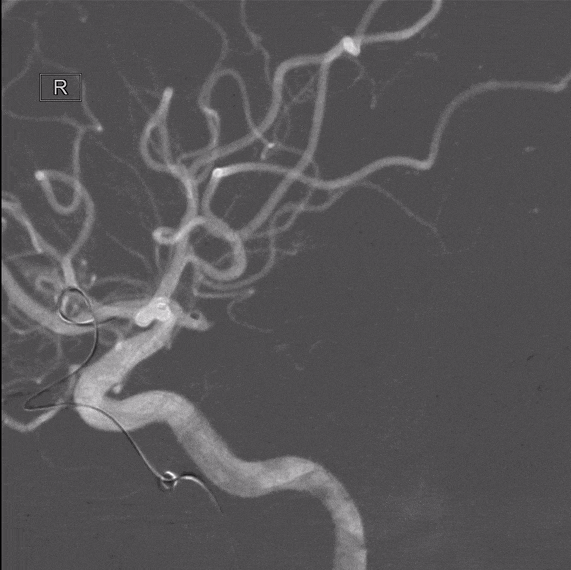

左侧颈内动脉造影

右侧颈内动脉造影

双侧椎动脉造影

压颈造影及压颈3D

栓塞微导管及支架导管到位

强生 2mm*4cm

支架(Atlas 3.0*15mm)半释放,微创神通 1mm*1cm未解脱

造影提示右侧A1动脉闭塞

回收弹簧圈、回撤栓塞微导管、支架全释放及使用替罗非班等处理

经处理后,载瘤动脉复通